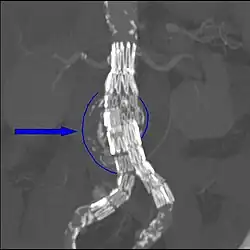

Abdominal aortic endograft on a CT scan; original aneurysm marked in blue

The procedure is carried out in a sterile environment under fluoroscopic guidance. It is usually carried out by a vascular surgeon, interventional radiologist or cardiac surgeon, and occasionally, general surgeon or interventional cardiologist.[9][10][11][12] The procedure can be performed under general, regional (spinal or epidural) or even local anesthesia.[13]